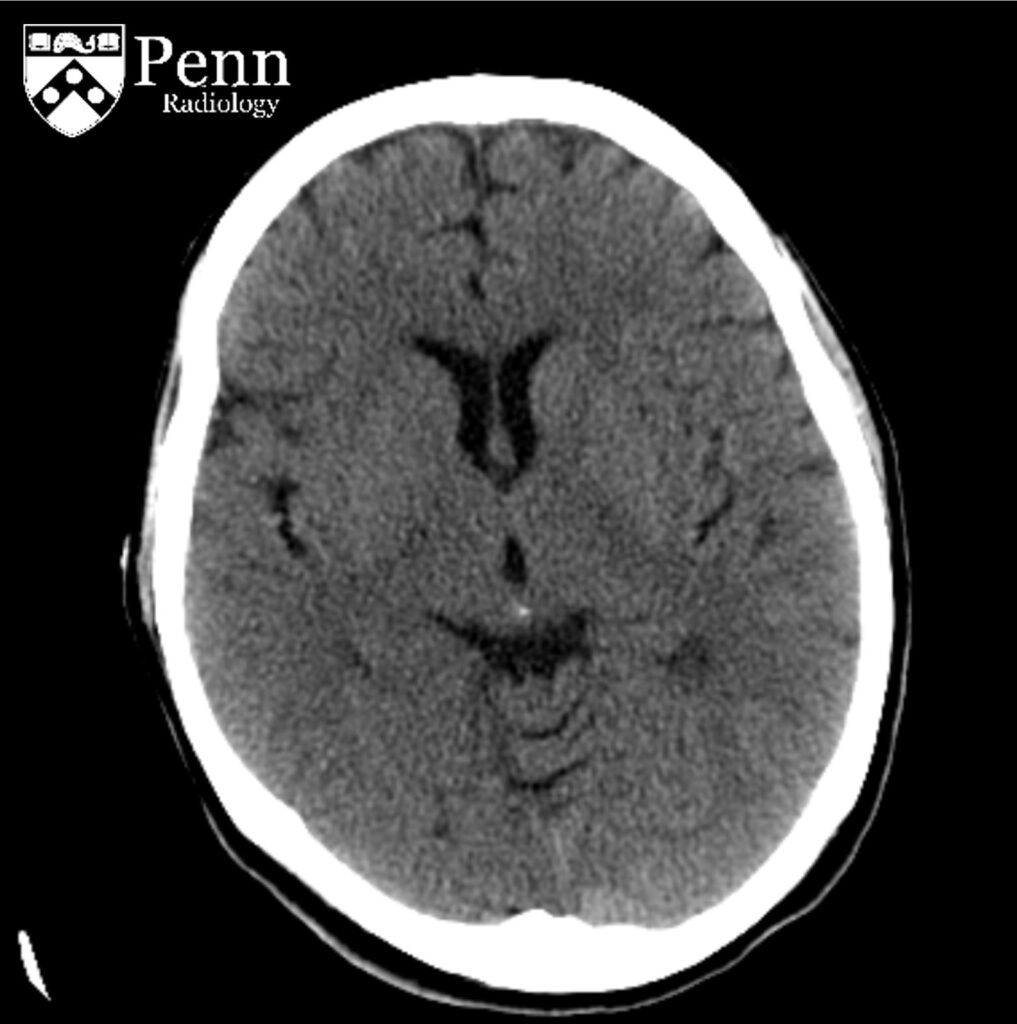

80-year-old man with altered mental status, seizure

An 80-year-old man with altered mental status and new-onset seizure one week after a fall.